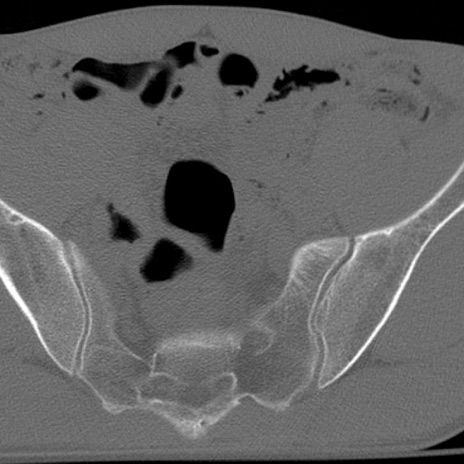

症例3 腰椎CT(横断像)

腰椎CT